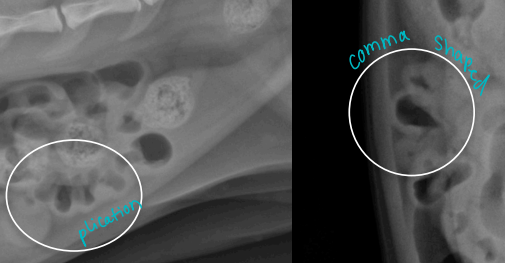

Intestinal Obstruction

Et: FB (#1), intussusception, neoplasia

More Proximal obx = more severe vomiting

Linear: #1 cause of Obx

Cats young (#1)→ base of tongue

Dogs older→ pylorus

Cs: Vomiting, dehydration, lyte imbalance, ± aneroxia, depression, abd. pain, ± shock/sepsis

Dt: PE, Palpation, survey Rads #1 ± contrast, US(more sensitive)

dilated loops, stacking, gas pattern

Comma-shaped gas bubbles

Tx: pre anes. fluids, Sx once stable, cut string under tongue,